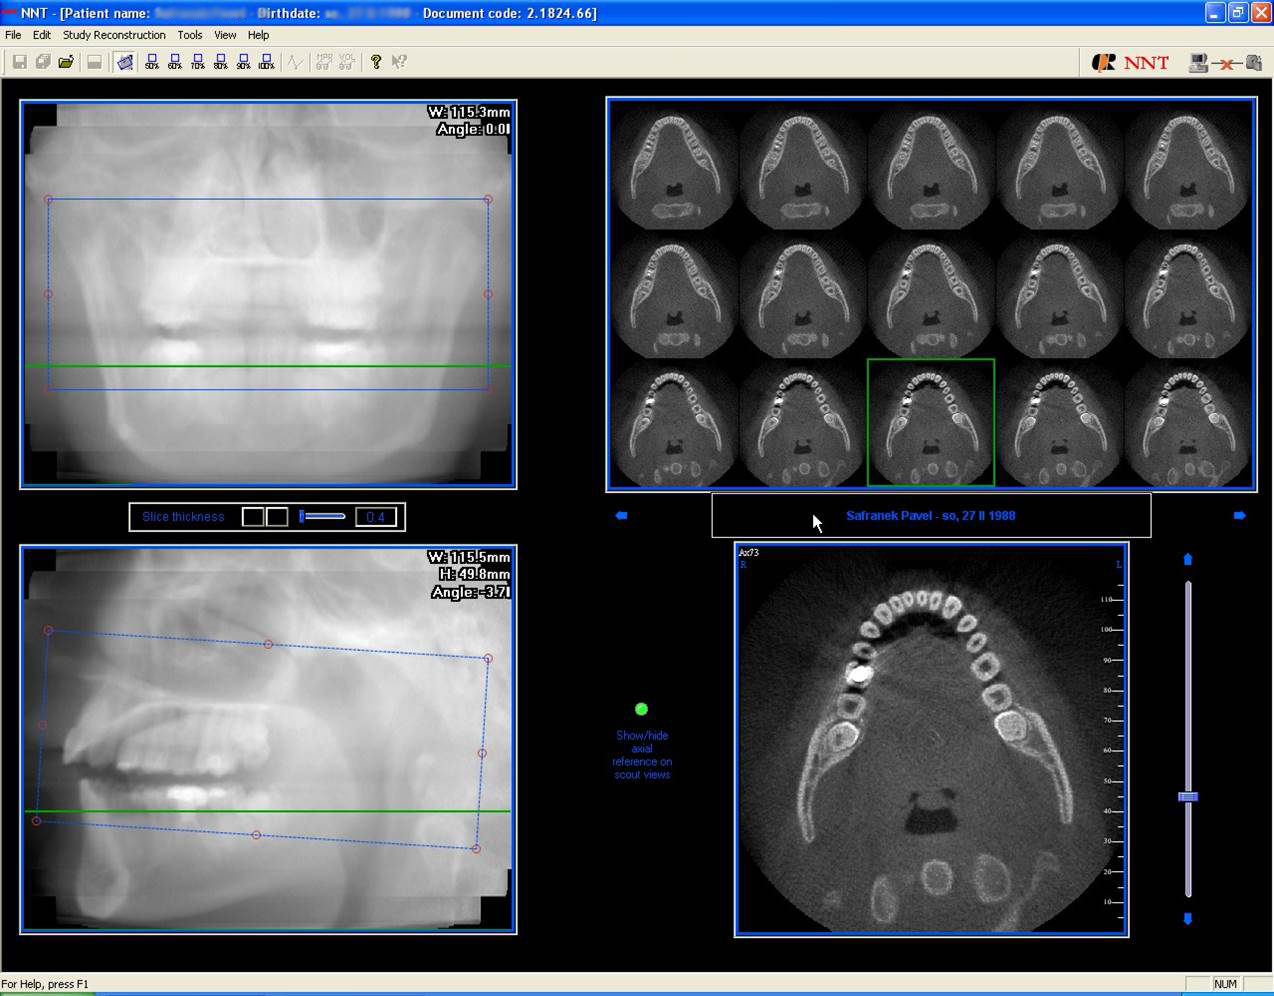

3D DVT - NewTom

Je speciální zubní digitální tříprostorový tomograf (3D), který umožňuje na základě jediného snímkování vytvořit všechny typy RTG zobrazení, které jsou pro lékaře potřebné. Díky používané technologii tzv. „kuželového paprsku“ a speciálním senzorům je výrazně zmenšená dávka záření - o více jak 80% proti klasickému CT vyšetření. To je významné zejména u dětí. Pomocí tohoto přístroje je možné zjisti skutečnou situaci v čelistních kostech pacienta tedy množství kosti - můžeme změřit skutečnou šířku i výšku kosti, i kvalitu kosti (hustotu) v místě uvažované implantace. 3D (tříprostorové) zobrazení umožňuje zvýšit prostorovou představu operatéra ještě před vlastní operací a zároveň pacientovi lépe objasnit a ukázat oblast plánovaného zavedení implantátu.

Pacient „neumí číst“ RTG snímky, ale díky 3D zobrazení vidí „svoji skutečnou čelist“ - např. jak je nízká či úzká, vidí průběh nervu nebo velikost čelistní dutiny, což mu umožní i pochopení nutnosti v některých případech provést pomocné zákroky ještě před vlastním zavedením implantátu (viz. kostní štěp, sinus lift, kostní granulát...).

Vyšetření pomocí tohoto přístroje používáme i ve stomatochirurgii (zlomeniny čelistí, zuby moudrosti, cysty, onemocnění čelistního kloubu), ortodoncii (retinované zuby, nadpočetné zuby), parodontologii atd.